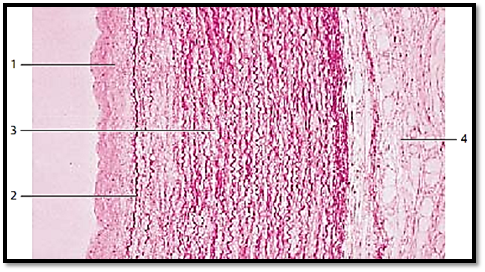

This cross-section of a thoracic aortic wall exemplifies a typical elastic artery. The tunica intima 1 , followed by the membrana elastica interna 2 adjoin the tunica media . The tunica me dia 3 consists of concentric layers of fenestrated elastic membranes, which are interspersed with myocytes, f ibrocytes, thin collagen fibrils and amorphous substances with a high chondroitin sulfate content. The undulating elastic f ibers stand out in vertical sections. Apart from collagen f ibers, the tunica adventitia 4 also contains elastic fibers, fibrocytes, adipocytes and vasa vasorum .

1 Tunica intima

2 Internal elastic membrane, membrana elastica interna

3 Tunica media

4 Tunica adventitia

Stain: hematoxylin-eosin-resorcin-fuchsin; magnification: × 80